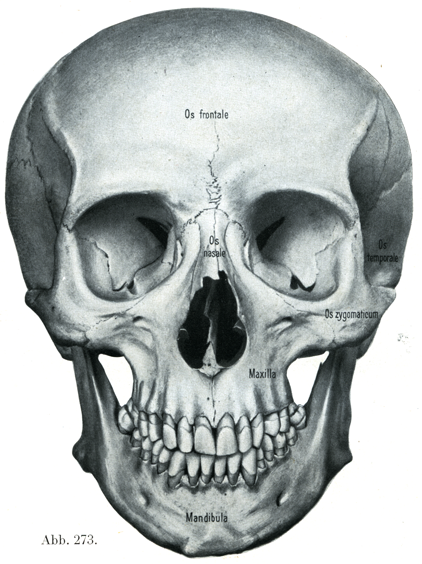

[図273]頭蓋(45才の男)前からみる(7/10) (ベルリン解剖学教室所蔵の標本)